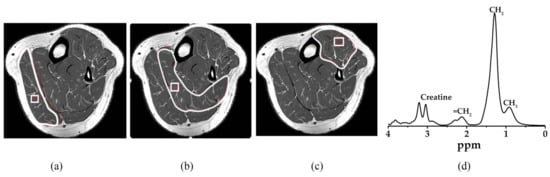

The same scanning parameters were used for muscular metabolite signals. Voxel 10 mm × 10 mm × 10 mm size was located on gastrocnemius, soleus, and tibialis anterior muscles respectively, avoiding the involvement of the intermuscular lipid and vascular structures as shown in Figure 4. The total triglyceride lipid from methyl (TG-CH3) and methylene (TG-CH2) protons of the gastrocnemius (G-TG), soleus (S-TG), and tibialis anterior (TA-TG) were obtained using the same method as the IHL analysis. The lipid content differences in each muscle spectrum involved the different fiber type composition and their metabolic activity. Spectrum fitting and quantification were done for water peak (4.7 ppm) and major lipid spectrum peaks -CH3 (0.9 ppm), -CH2 (1.3 ppm), and (2.1 ppm) with prior knowledge [45].

Figure 4. MR spectra were acquired; Voxel (10 mm × 10 mm × 10 mm) localization on (a) gastrocnemius muscle, (b) soleus muscle, (c) tibialis anterior muscle, and (d) MRS spectrum with major lipid spectrum peaks CH3 (0.9 ppm), CH2 (1.3 ppm), and (2.1 ppm). The pixel value that appears as white and black in the binary image represents adipose tissue content and soft tissue, respectively. The gastrocnemius, soleus, and tibialis anterior muscle area were determined through manual drawing in the region of interest. White line: Region of interest, White square: Voxel, CH3: Methyl, CH2: Methylene.